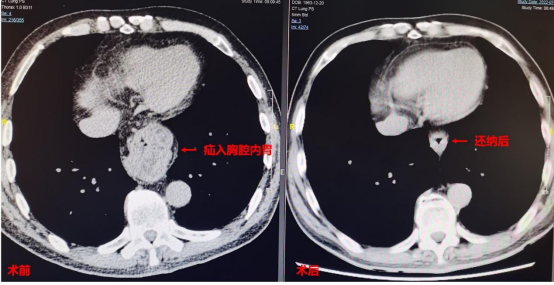

常浩教授经过仔细评估患者病情,发现患者反流症状较重,且既往有腹部手术史,腹腔可能存在广泛粘连。常浩教授决定应用达芬奇机器人为患者施行手术,最大程度做到精细化及减少创伤。经过严密的术前准备,手术采用全孔机器人手术方式以减少创伤,手术顺利进行。术中常浩教授发现患者食管裂孔扩大明显,胃底及部分胃体疝入胸腔,经过精细的分离,最终将疝入胸腔的胃还纳回腹腔,缝合修补扩张的食管裂孔,恢复腹段食管长度,并进行胃底折叠抗反流手术(Dor手术)。在达芬奇机器人清晰的视野及精准操作下术中几乎无渗血。患者术后恢复顺利,术后3日即进食出院,且反流症状明显好转。

手术前后胸部CT